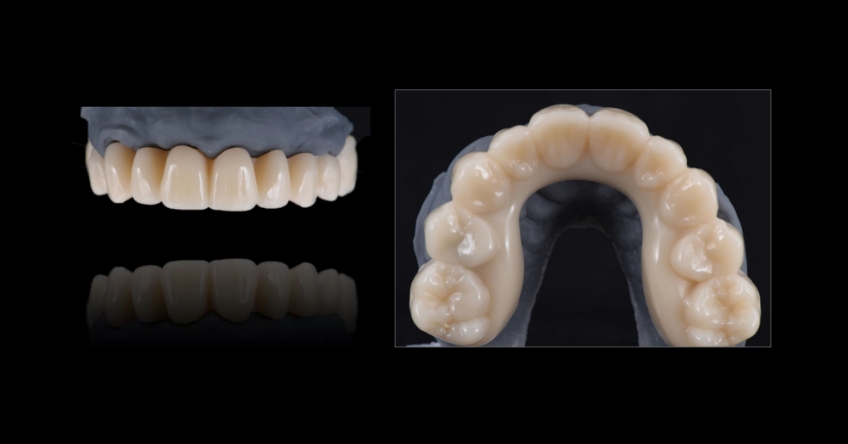

Ultimately, the patient was treated using a combination of traditional and zygomatic implants, allowing her to transition into the definitive prosthesis uneventfully and in a reasonable time frame. This prosthetic design aimed to improve the distribution of occlusal forces and provide enhanced structural support for the final prosthesis.

Comparing zygomatic implants (ZI) vs. bone grating can affect the outcome for your patient. The selection of the proper combination of traditional and ZIs is based on the amount of residual maxillary alveolar bone, the biomechanical requirements of the final dental implant rehabilitation, finances, and surgeon and restorative dentist preferences and experience. The most critical factor for success is the establishment of a prosthetically driven treatment plan between the surgeon and the restorative dentist.